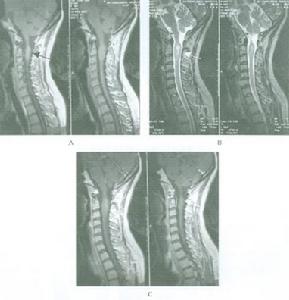

3.MRI 多為信號不均勻的長T1長T2病變,呈結節狀矢狀位有利於區分腫瘤與四腦室底小腦蚓部的位置關係和向椎管內伸延的長度(圖1,2)。

顱後窩室管膜瘤——圖2手術切除為首選治療手段。因腫瘤多與腦幹和後組腦神經粘連,使手術全切除率降低,術中加強神經電生理監測將有利於更完全切除腫瘤,減少術後併發症和死亡率。對於自四腦室底長出的腫瘤不必勉強全切,可殘留一薄層腫瘤組織在四室底,以免損傷面丘和腦幹但手術務必使腦脊液梗阻恢復通暢。室管膜瘤對放療中度敏感應對殘餘腫瘤和全腦、椎管實行放療。而且為了防止原發灶外的種植轉移的發生,對無轉移的間變型腫瘤也應行預防性全腦脊髓放射治療。室管膜瘤較髓母細胞瘤化療敏感性更差,大劑量化療也不能產生顯著療效。但也有學者認為化療能使殘餘腫瘤增殖受到抑制,在二次手術時易從腦幹和腦神經處進行剝離。